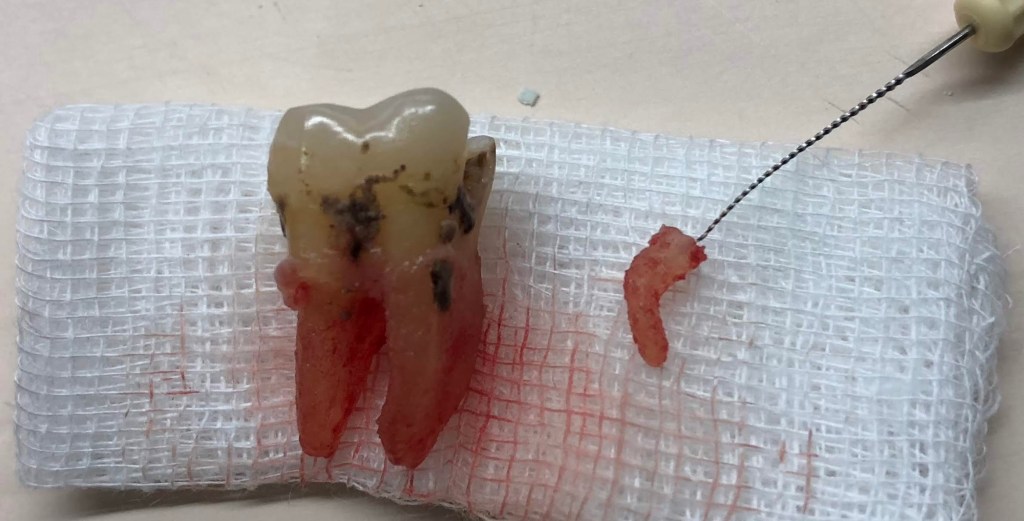

Don’t Remove. (before X-ray) radix-ento พบได้ในคนไทย 12.7% Germination X-ray ช่วยให้เห็นสิ่งที่ซ่อนอยู่ภายใน สังเกต furcation ก็รู้ว่าฟัน Perio Mermaid Premolar ให้สังเกตที่ mouth mirror เห็นถึงความฝ้ามัว เป็น Br พม่าครับ alloy ไม่แข็งมาก X-ray เท่านั้นจึงจะรื้อได้ ผมจะชอบวัดความยาวของฟันบ่อยๆ เทียบกับความยาวในใจที่เดาเอาไว้ RCT incomplete ใครสังเกตเห็นความผิดปกติบ้างครับ? ถึงกับต้องถ่ายทุกมุมเลยซี่นี้ remove ฟัน Crowding เป็น PVC ล้อมด้วยฟัน RCT อย่าลืม X-ray ก่อนถอนนะครับ Share this: Share on X (Opens in new window) X Share on Facebook (Opens in new window) Facebook Like Loading... Uncategorized